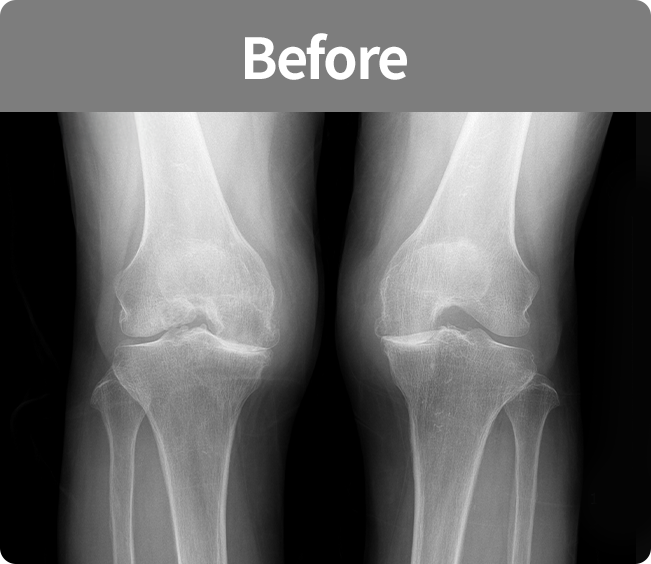

인공 관절 치환술

퇴행성관절염 및 기타 관절손상으로 통증이 심해

정상생활을 할 수 없고 다른 치료나 시술로 효과가 없는 경우에 시행하는 수술법(부분 치환술, 전 치환술)